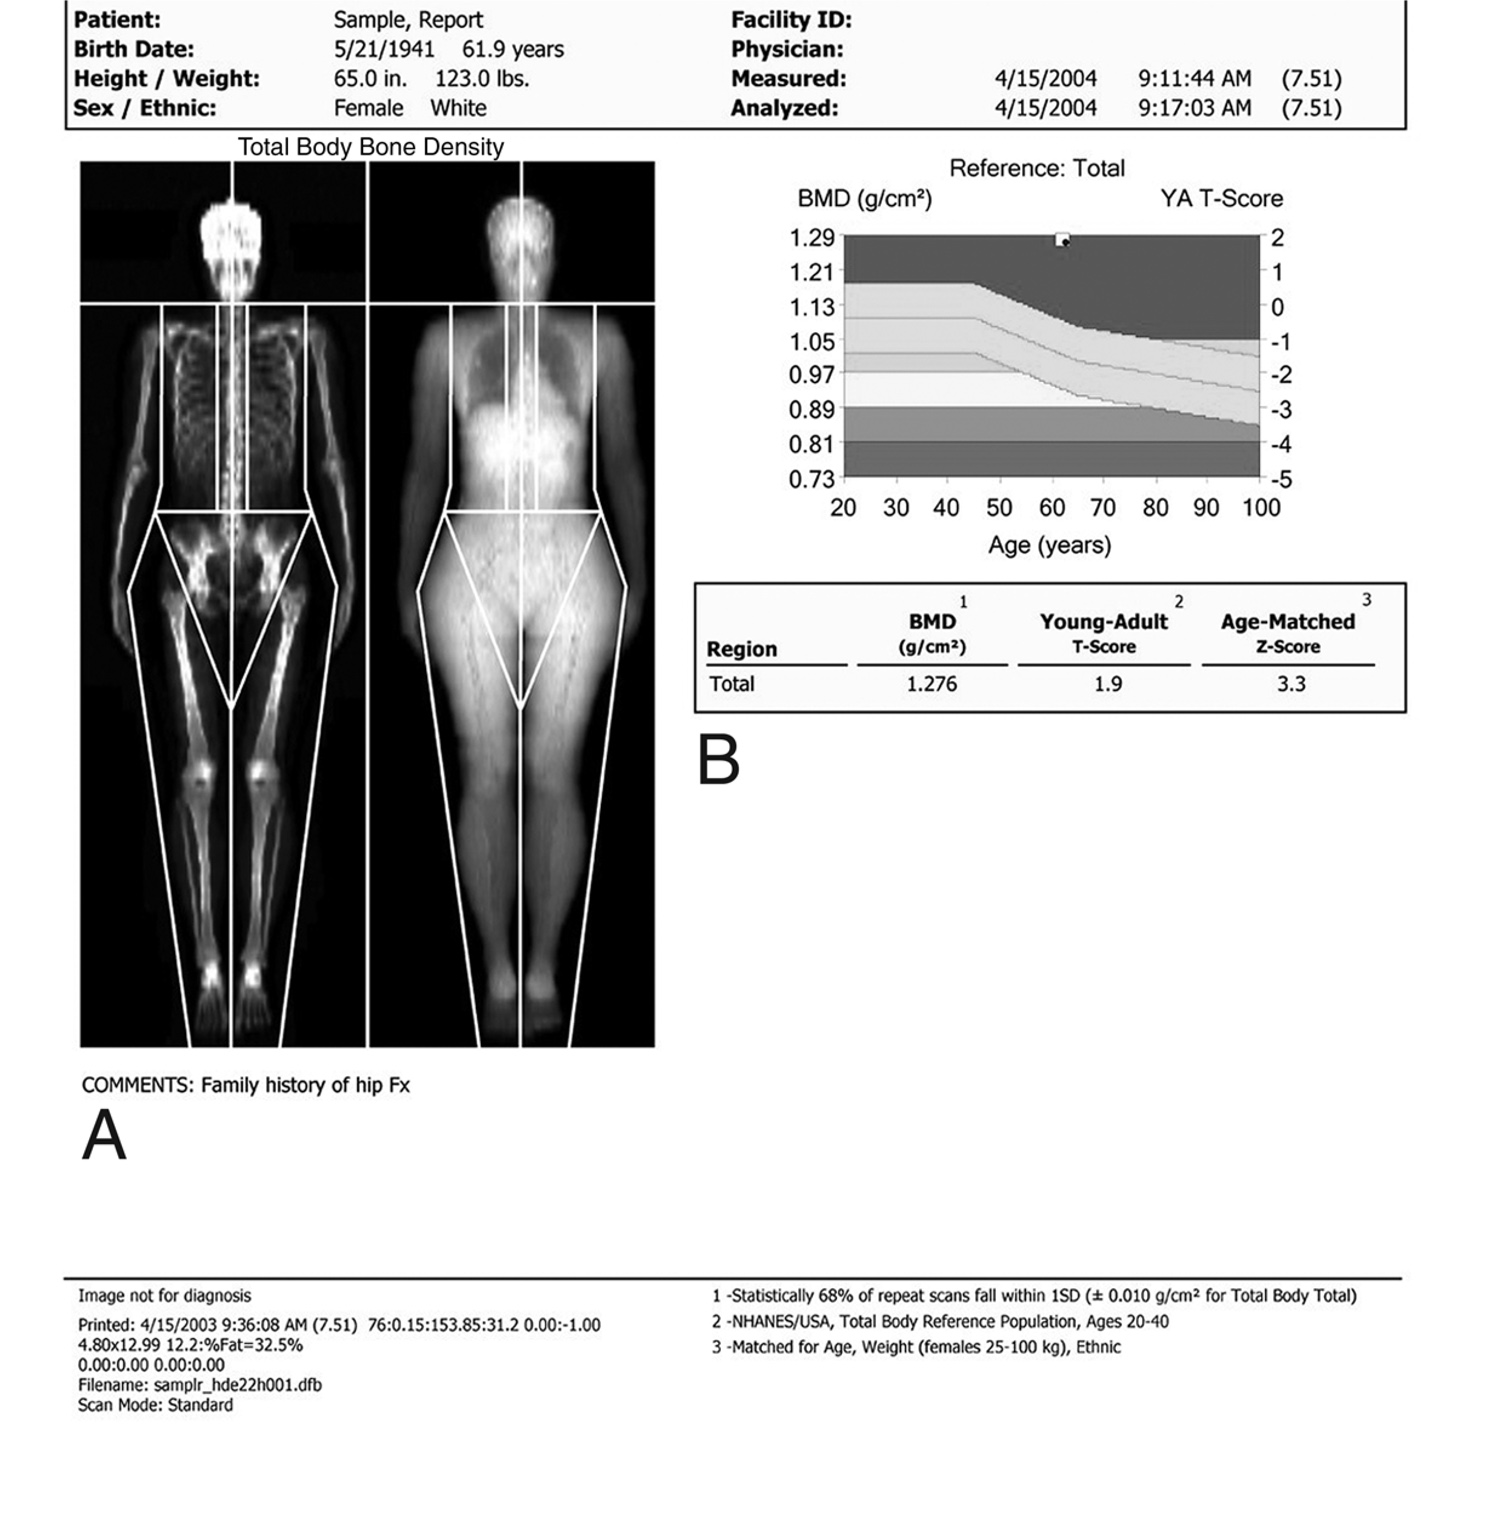

Duel-energy x-ray absorptiometry (DXA) scan

A duel-energy X-ray absorptiometry (DXA) scan is the "gold standard" of bone mineral density testing.

Reproduced with permission from JF Sarwark, ed: Essentials of Musculoskeletal Care, ed 4. Rosemont, IL, American Academy of Orthopaedic Surgeons, 2010